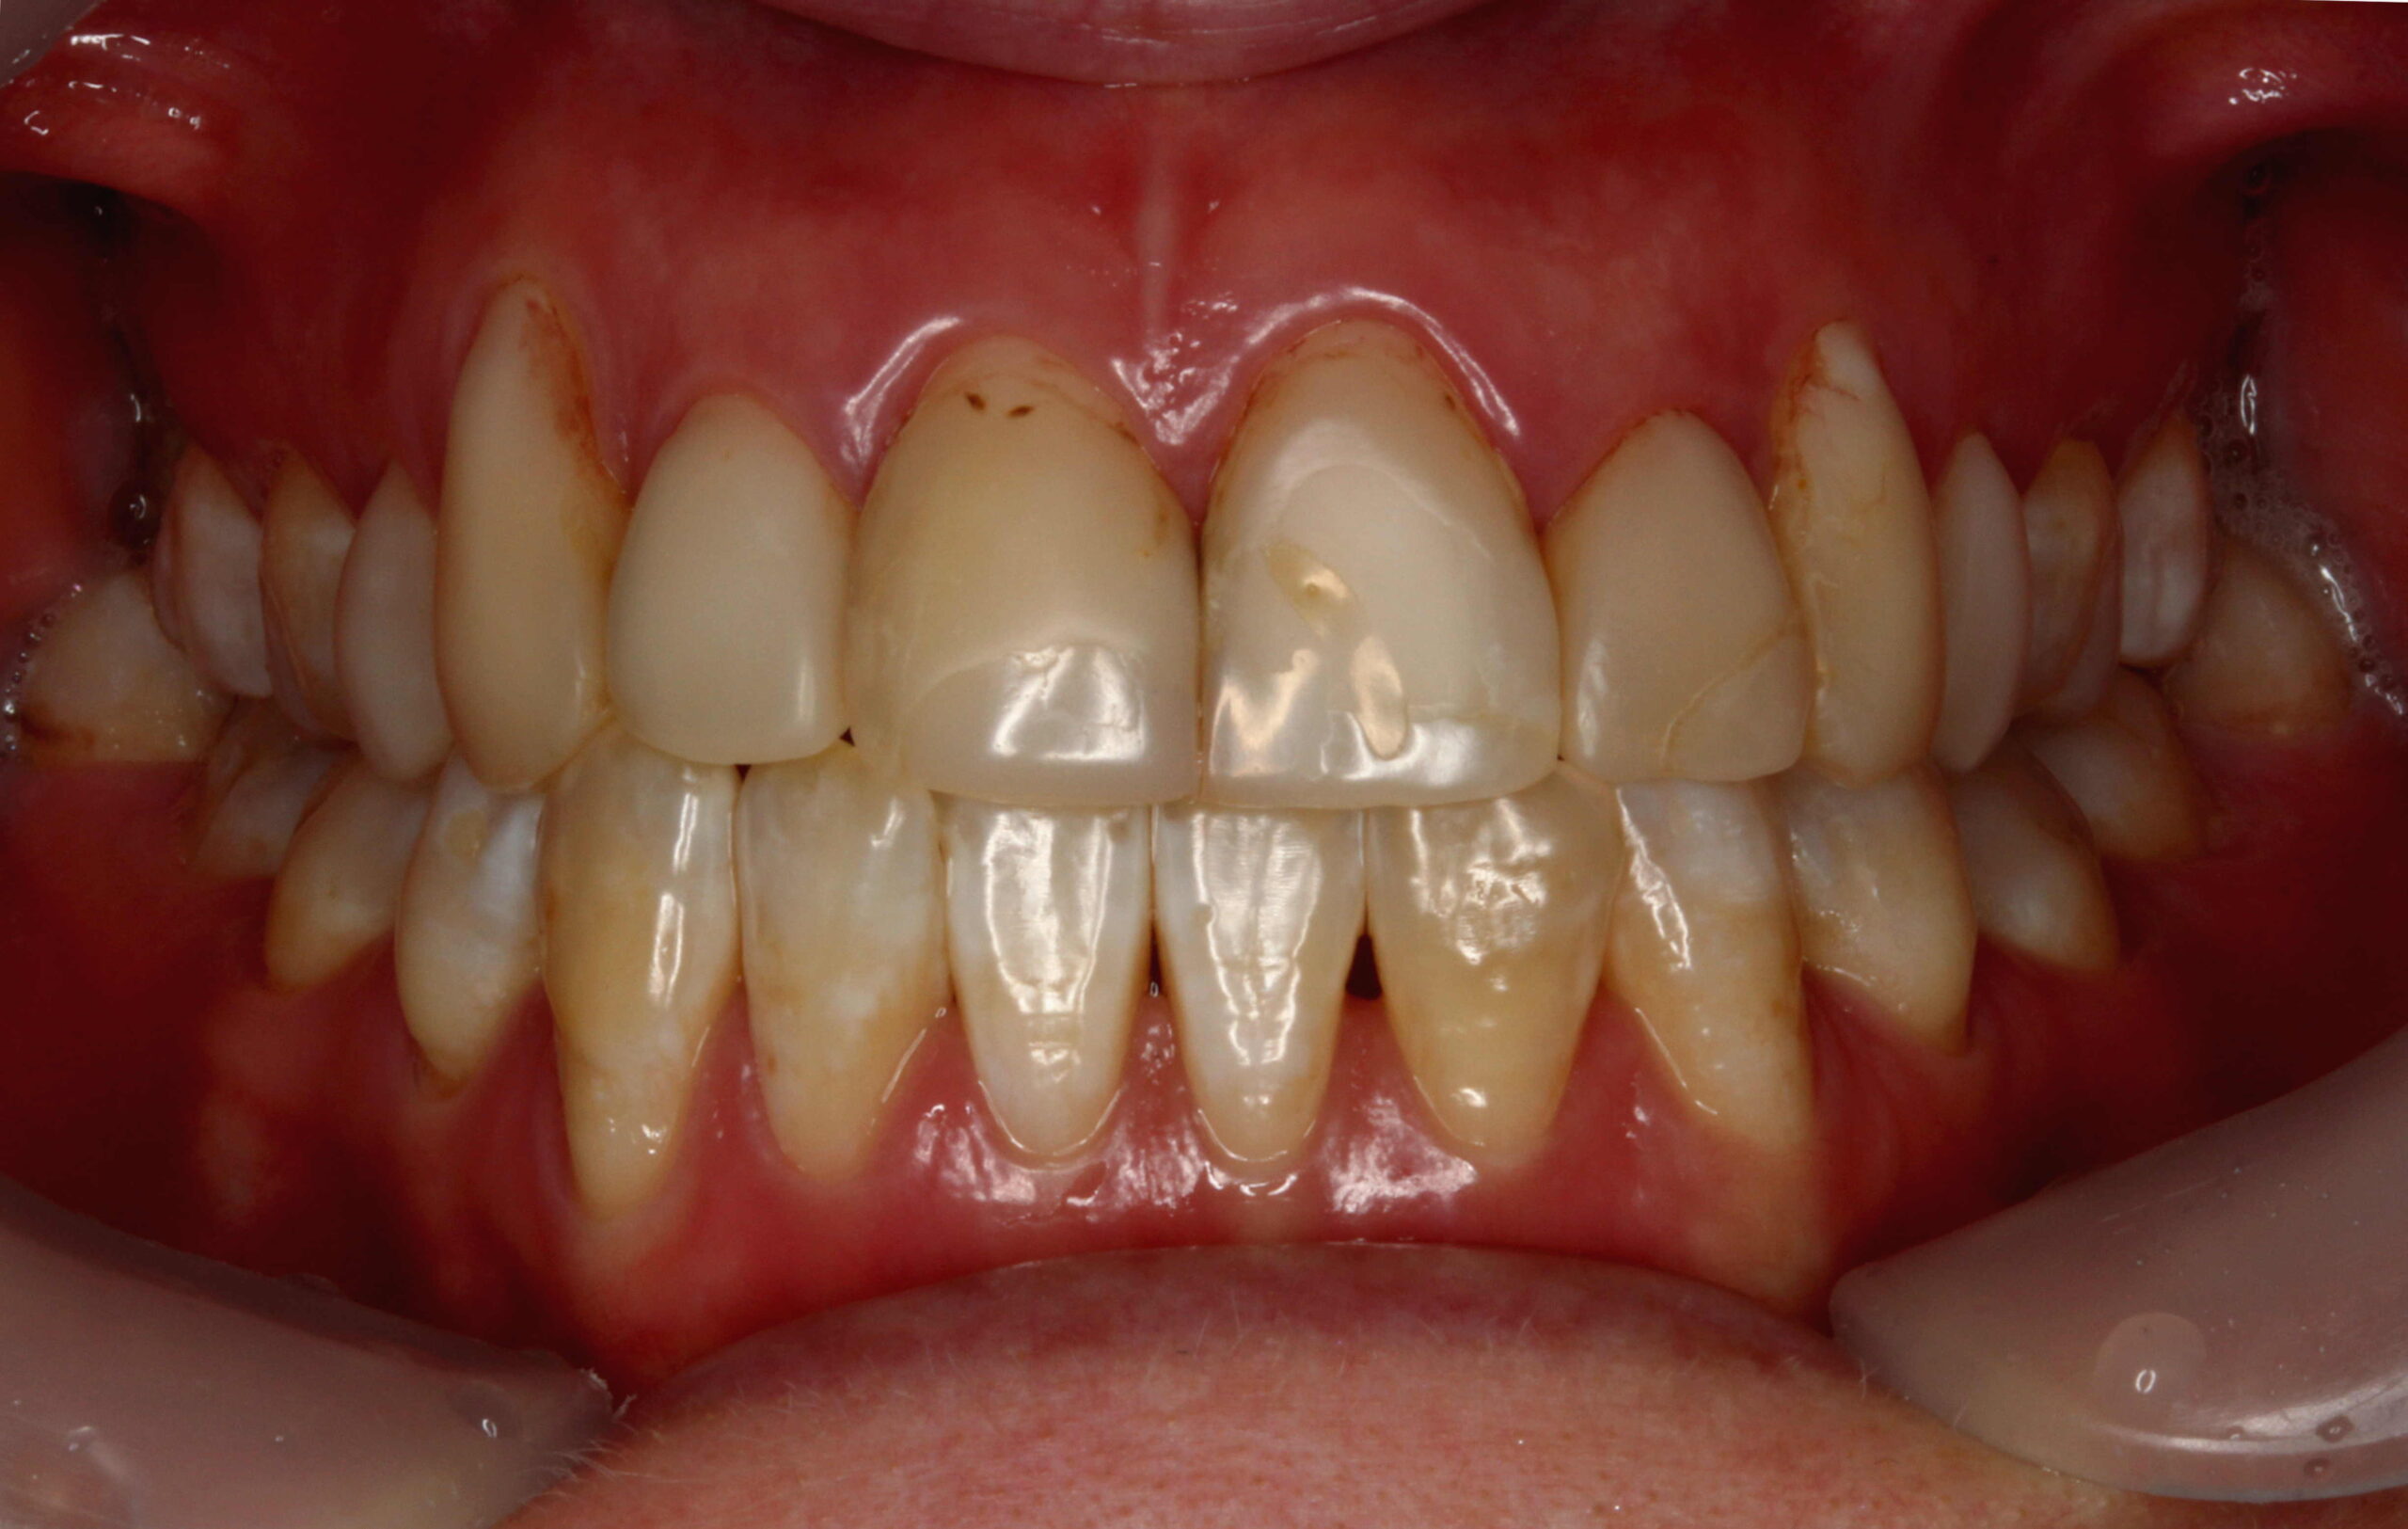

前歯6本の削らないラミネートベニア症例です。

古くなったレジンベニア(プラスチック)が着色し歯の色が気になっている方の症例です。

自然な仕上がりを希望の方で、レジンベニアと虫歯を除去して元の歯に近い形や歯並びで削らないラミネートベニアを作成しました。

削らないラミネートベニアの色は周りの歯に合わせて控えめな白さで作成し、とても自然な仕上がりになりました。

削らないラミネートベニアe.maxはオールセラミックなので、レジン(プラスチック)よりも衛生的で健康的です。